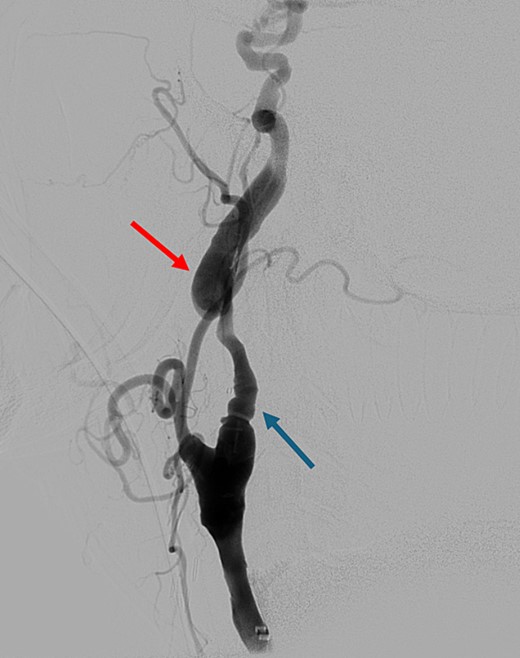

On presentation to the hospital, he was found to be in hypertensive crisis. Non-contrast head CT scan showed moderate volume biconvexity SAH (Fig. 1). CT angiography (CTA) of his head and neck showed a left internal carotid artery (ICA) dissection extending from the mid cervical segment to the level of the vertical petrous segment. Six vessel digital subtraction angiography confirmed a left ICA dissection extending from the proximal mid cervical ICA into the petrous segment. In the same region, there was also a left pseudoaneurysm formation with slight turbulent flow and stagnation (Fig. 2).

Non-contrast axial head computed tomography scan demonstrating biconvexity subarachnoid hemorrhage.